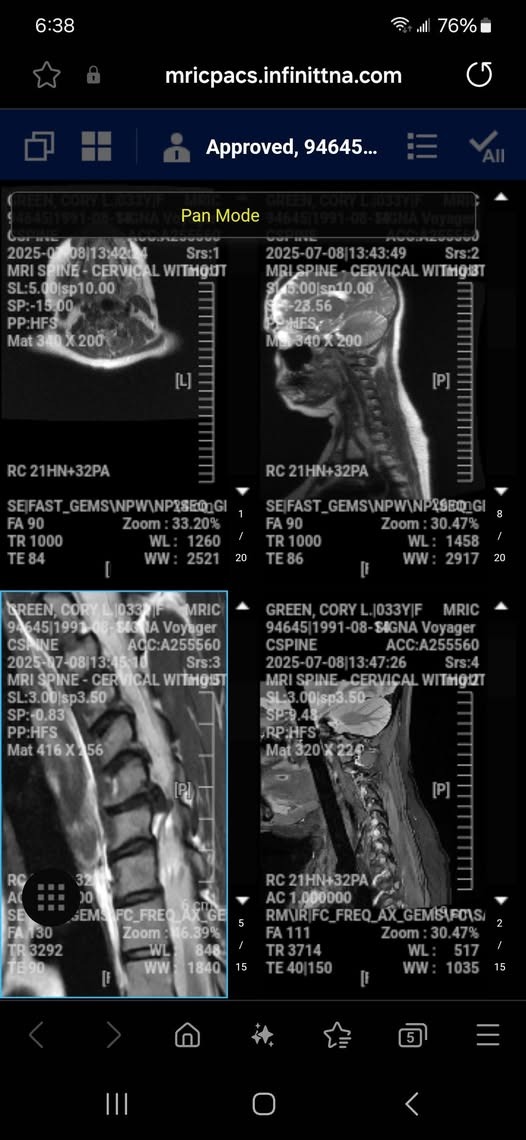

My health journey the last 3 or so years has been rough, to say the least. I was able to finally start battling my Lyme disease, and then something in my body decided to shift. I ended up with a debilitating muscle spasm that actually pulled and rotated my cervical spine, my neck, and in doing so gave me something called "torticollis." Unbeknownst to me, I had multiple bone spur complex growths on multiple vertebrae in my neck. When the twisting occurred, the bone began cutting into my spinal cord, causing some significant damage. I can no longer feel my thumb or first two fingers at all on my right hand. I am in excruciating pain, and my quality of life is minimal. I have 2 bulging disks in my neck, both of which require full removal.

The surgery I will be getting removes both disks, shaves off the osteophytes, and uses them to create a paste that is then inserted where the disks were. A cage is placed around four of my vertebrae, and then they will all fuse into one column, for lack of a better term. I have many, many out-of-pocket costs. My husband will have to be out of work for six weeks minimum as I will be in for a long and painful recovery.

If you could donate anything at all, it would go towards our medical costs, bills and co-pays, gas, a device that stimulates bone growth, normal expenses, and bills as my husband will be out of work for 6 weeks minimum. I believe someone is also setting up a meal train for our family if that is more your style; we would love some home-cooked meals to pop in the oven. All prayers and good healing vibes are appreciated and welcome. If you can help, that would mean the world to us, and even if you cannot, please share :) I have attached a screenshot of my most recent MRI scan. The white long thing is my spinal cord; the black pressing into it is my bone. Some pretty severe nerve damage has been done, unfortunately, and the sooner I can get this surgery, the more chance of healing my nerves.